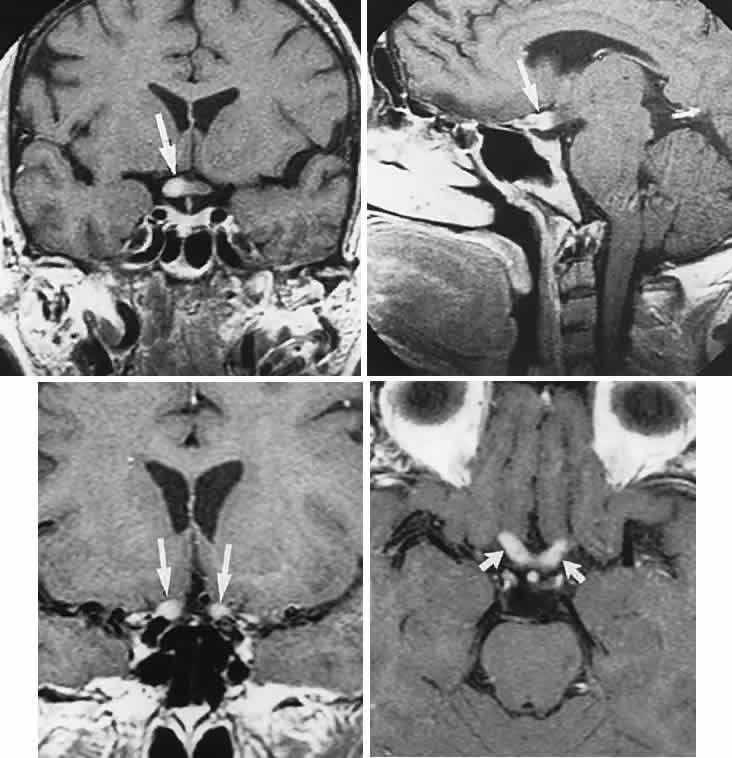

CONGENITAL HAMARTOMA SYNDROMES

The “neurophakomatoses” are a diverse group of disorders nosologically related by the presence of hamartomatous lesions, and, indeed, the term “hereditary hamartomatosis” is a more accurate description. However, whereas neurofibromatosis, tuberous sclerosis, and von Hippel-Lindau disease are transmitted with irregular dominance and considerable variation in penetrance, no hereditary basis of Sturge-Weber or angio-osteohypertrophy (Klippel-Trenaunay-Weber) syndrome has been established.

A hamartoma is a tumor of anomalous origin composed of elements normally present in the tissue in which it originates and with a limited capacity for proliferation. The following tumors may be classified as hamartomas: (1) in neurofibromatosis: optic gliomas (see Chapter 6), neurofibromas, and ganglioneuromas; (2) in tuberous sclerosis: retinal and cerebral astrocytomas, cutaneous angiofibromas (“adenoma sebaceum”), rhabdomyomas, and leiomyomas; (3) in von Hippel-Lindau disease: hemangioblastomas of the cerebellum and retina (including optic nerve head) and renal hypernephromas or cysts; (4) in Sturge-Weber disease: facial and choroidal cavernous hemangiomas and meningeal angiomatous malformations; and (5) in Klippel-Trenaunay-Weber syndrome: cutaneous nevi, visceral and limb hemangiomas, and orbitofacial venous varices.

If all disorders with neurocutaneous manifestations are considered, the term phakomatoses (Greek, phakos, “spot,” “birthmark”) is appropriate, and the catalog of “related” disorders becomes cumbersome. “The Phakomatoses,” Volume 14 of Vinken and Bruyn's Handbook of Clinical Neurology, is extraordinarily complete and serves as a source of detailed clinical descriptions of these diseases.146 Syndromes characterized by vascular hamartomas, that is, retinal-cerebellar angiomatosis (von Hippel-Lindau), and other angiomatous malformations, are discussed in Volume 2, Chapter 17.

TUBEROUS SCLEROSIS

Tuberous sclerosis, so-called because of cerebral tubers (potatoes), is a multiorgan complex that often shows the stigmata of retinal astrocytic hamartomas in epipapillary and parapapillary locations, as well as in the retinal periphery (Fig. 10; see Color Plate 5-1B). These characteristic lesions appear as elevated semitransparent domes in the nerve fiber layer of the retina and may undergo calcification as the patient ages. The calcified hamartomas, when on or near the optic disc, have been termed “giant drusen.” These tumors should not be confused with the much more common drusen (hyaline bodies; see Part II of this chapter, Optic Nerve) within the substance of the nerve head, which are nonhamartomatous lesions and are not characterized by astrocytic hyperplasia. There is no evidence to support the suggestion that hyaline bodies of the optic disc are minor manifestations of tuberous sclerosis.